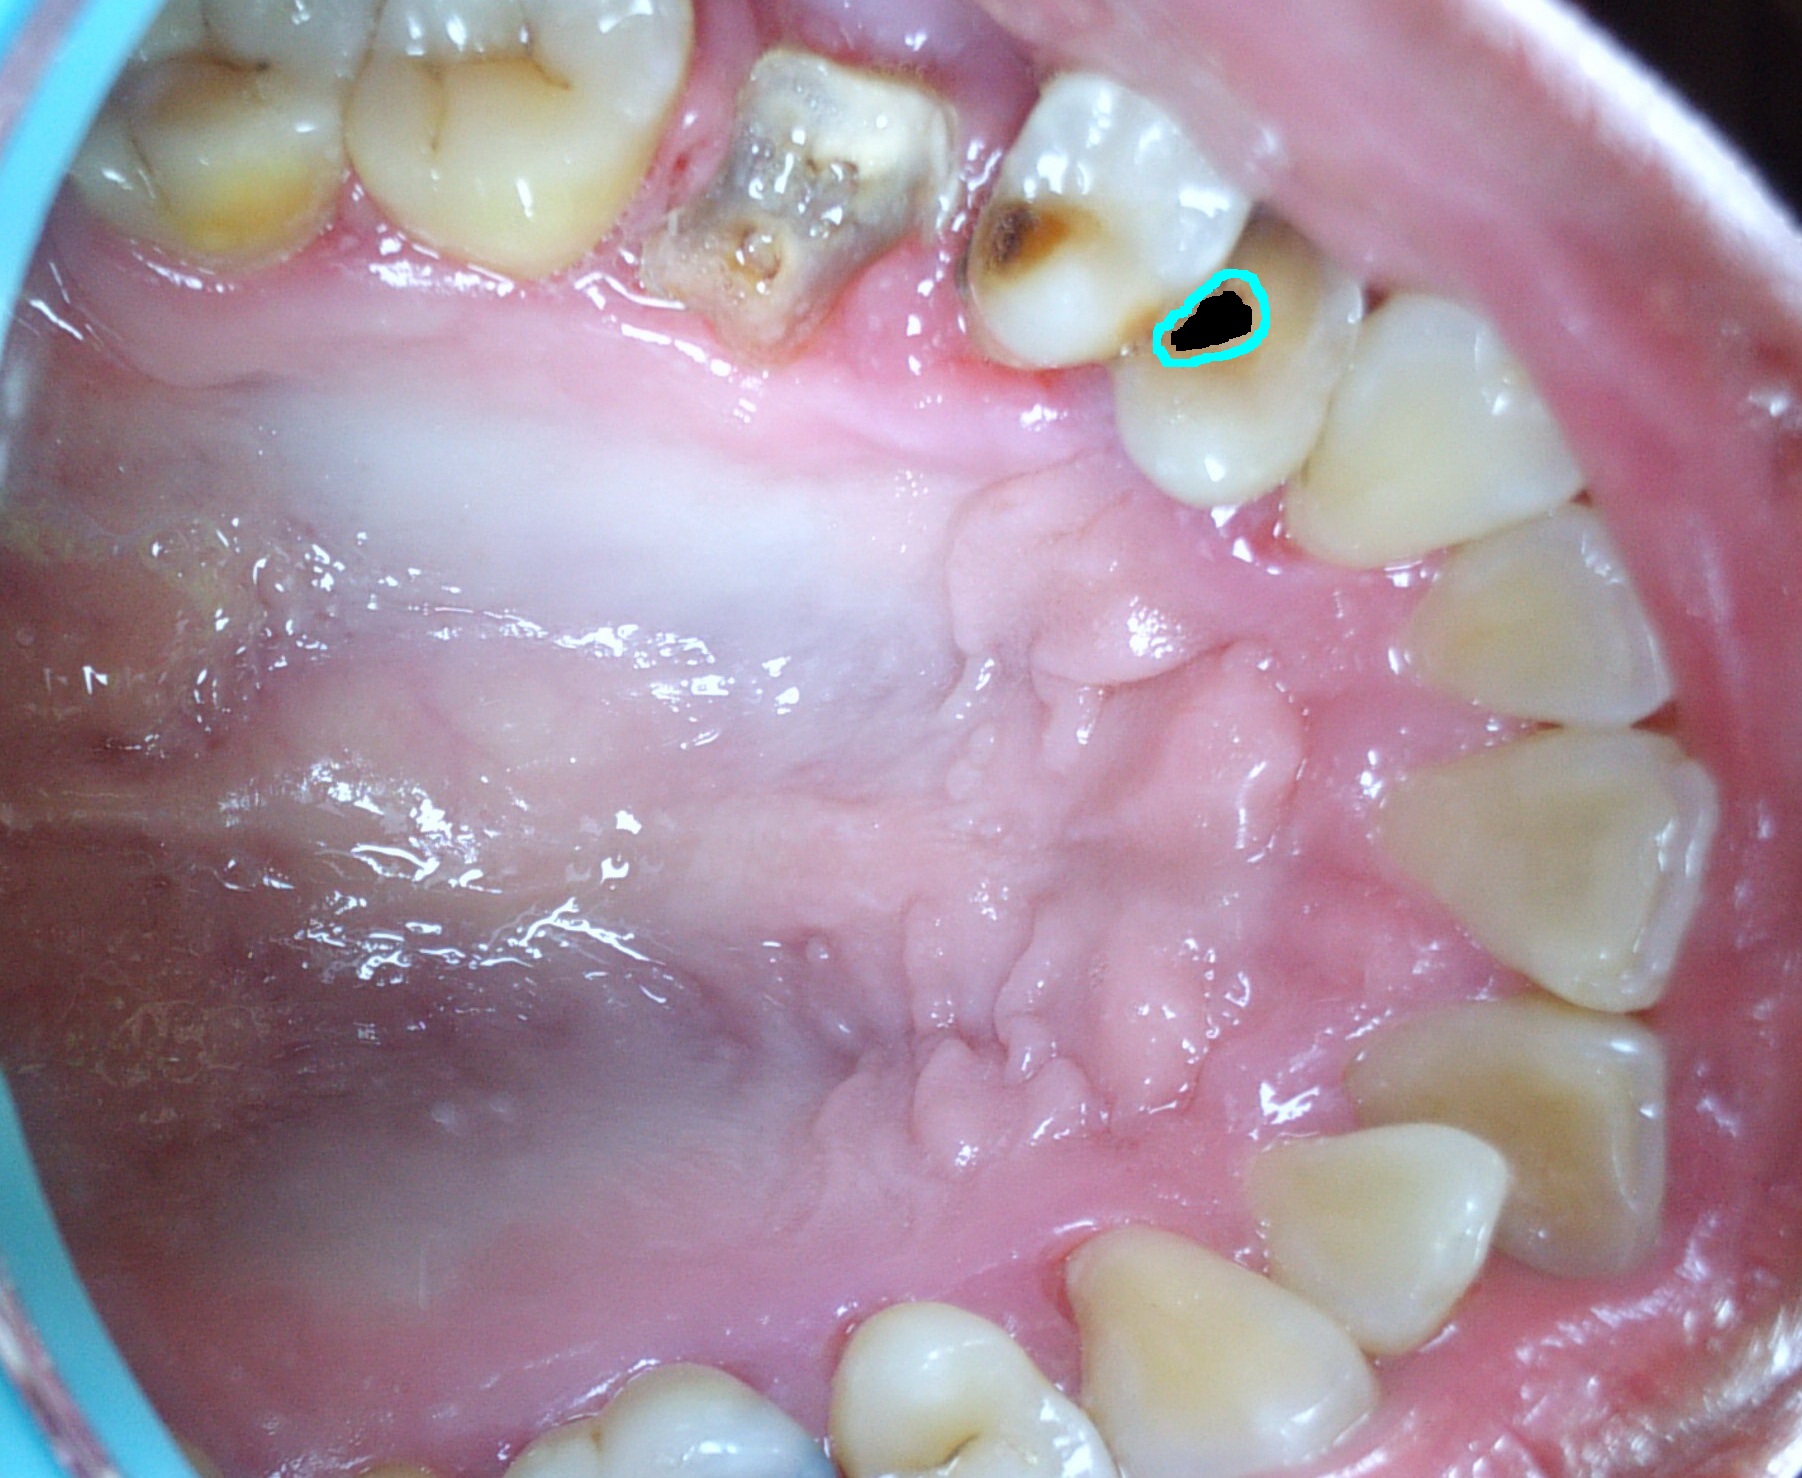

ฟันของลุงนักอมน้ำเกลือในตำนาน ได้มีการผุเป็นรูเพิ่มอีกหนึ่งซี่ ต่อไปรูก็อาจจะขยายหรือค่อย ๆ แตกสลายไปเหมือนฟันกรามก็เป็นได้

ประมาณสามสี่หรือห้าหกวันที่ผ่านมา

ผมเริ่มสัมผัสได้ว่าตรงฟันด้านบนซ้ายมันได้มีรูเกิดขึ้น

จึงได้ไปส่องกระจกดู ก็จึงได้พบว่ามันอยู่ในตำแหน่งแบบในรูปนี้